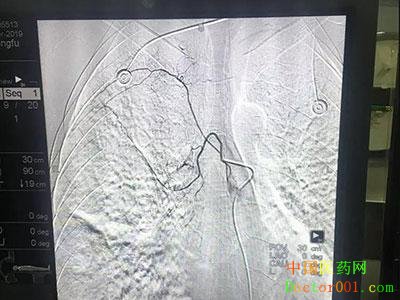

近日,重庆宏仁一医院呼吸消化内科在重庆急救中心孙小龙教授的带领下为一位52岁患者成功施行支气管动脉栓塞术。 《案例》详情: 患者,男,52岁,因“反复咳嗽、咯血1个月”于2019年4月17日在我院呼吸消化内科住院,入院后予立止血、酚磺已胺、维生素k1、垂体后叶素、卡洛癀等药物止血,效果不理想。 手术过程 住院期间患者反复呼吸道活动性出血,甚至出现大咯血,随时可能发生呼吸道窒息而危及生命,为及早控制病情,减轻患者痛苦,经反复与患者本人和家属的沟通后,于2019年4月30日在呼吸消化内科、放射科、介入中心医护人员的配合下由重庆急救中心介入科孙小龙教授为患者施行了支气管动脉栓塞介入术,术中在局麻下以Seldinger法穿刺右股动脉成功后置入5F动脉鞘,经导管注入PVA,造影复查染色消失,栓塞效果满意。1小时后安全返回病房,术后未发生咯血,于5月5日好转出院。